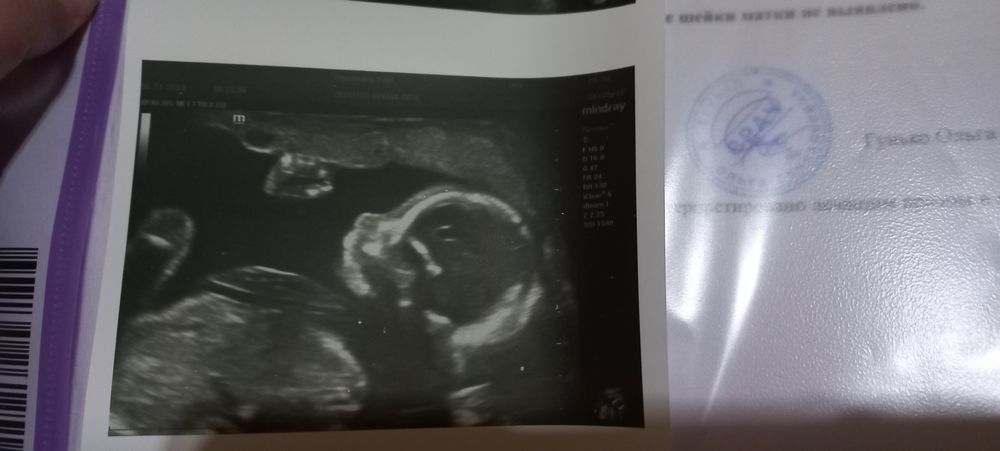

Результаты 2го скрининга!

Всё о нашей беременностиСегодня была на 2-м скрининге, на сроке 19,6)

Шейка 37, прошлое измерение на 17 неделе 35). С малышом всё хорошо, растёт наш кроха 345 грамм.

Есть предлежание плаценты, но узист успокоил, сказал, что часто до 3 скрининга поднимается и мне достаточно, чтобы на 2-4 см поднялась.